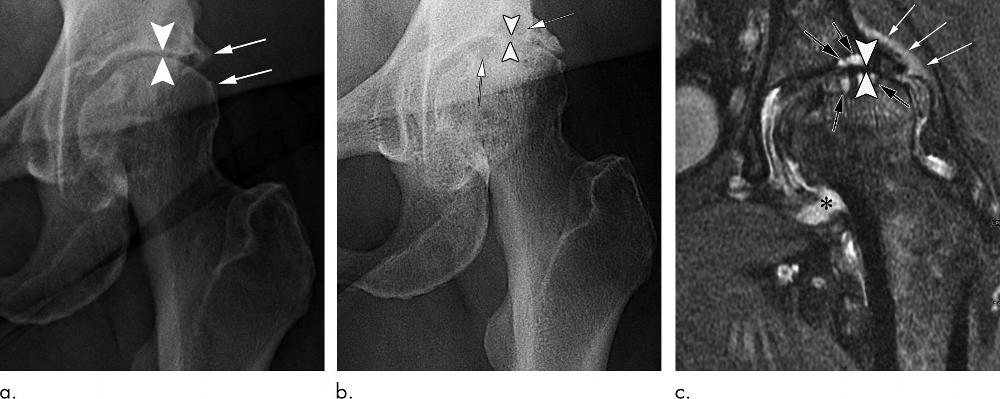

Figure 1. Rapid progressive osteoarthritis joint space loss (type 1) in a 61-year-old woman who presented with hip pain. (a) Anteroposterior left hip radiograph shows joint space narrowing (arrowheads) and femoral and acetabular osteophytic changes (arrows) consistent with Kellgren-Lawrence grade III hip osteoarthritis. She was referred for US-guided steroid injection. (b) Four months after intraarticular corticosteroid injection, she presented with worsening left hip pain. Anteroposterior hip radiograph shows severe interval joint space narrowing (arrowheads) and enlarging subchondral cysts (arrows). (c) Coronal intermediate-weighted fat-suppressed MRI obtained at the same time as b shows complete loss of the acetabular and femoral cartilage (arrowheads), with subchondral cystic changes (black arrows). In addition, there is joint effusion and synovitis (*) and periarticular soft-tissue edema (white arrows). This patient underwent total joint replacement 3 months later.